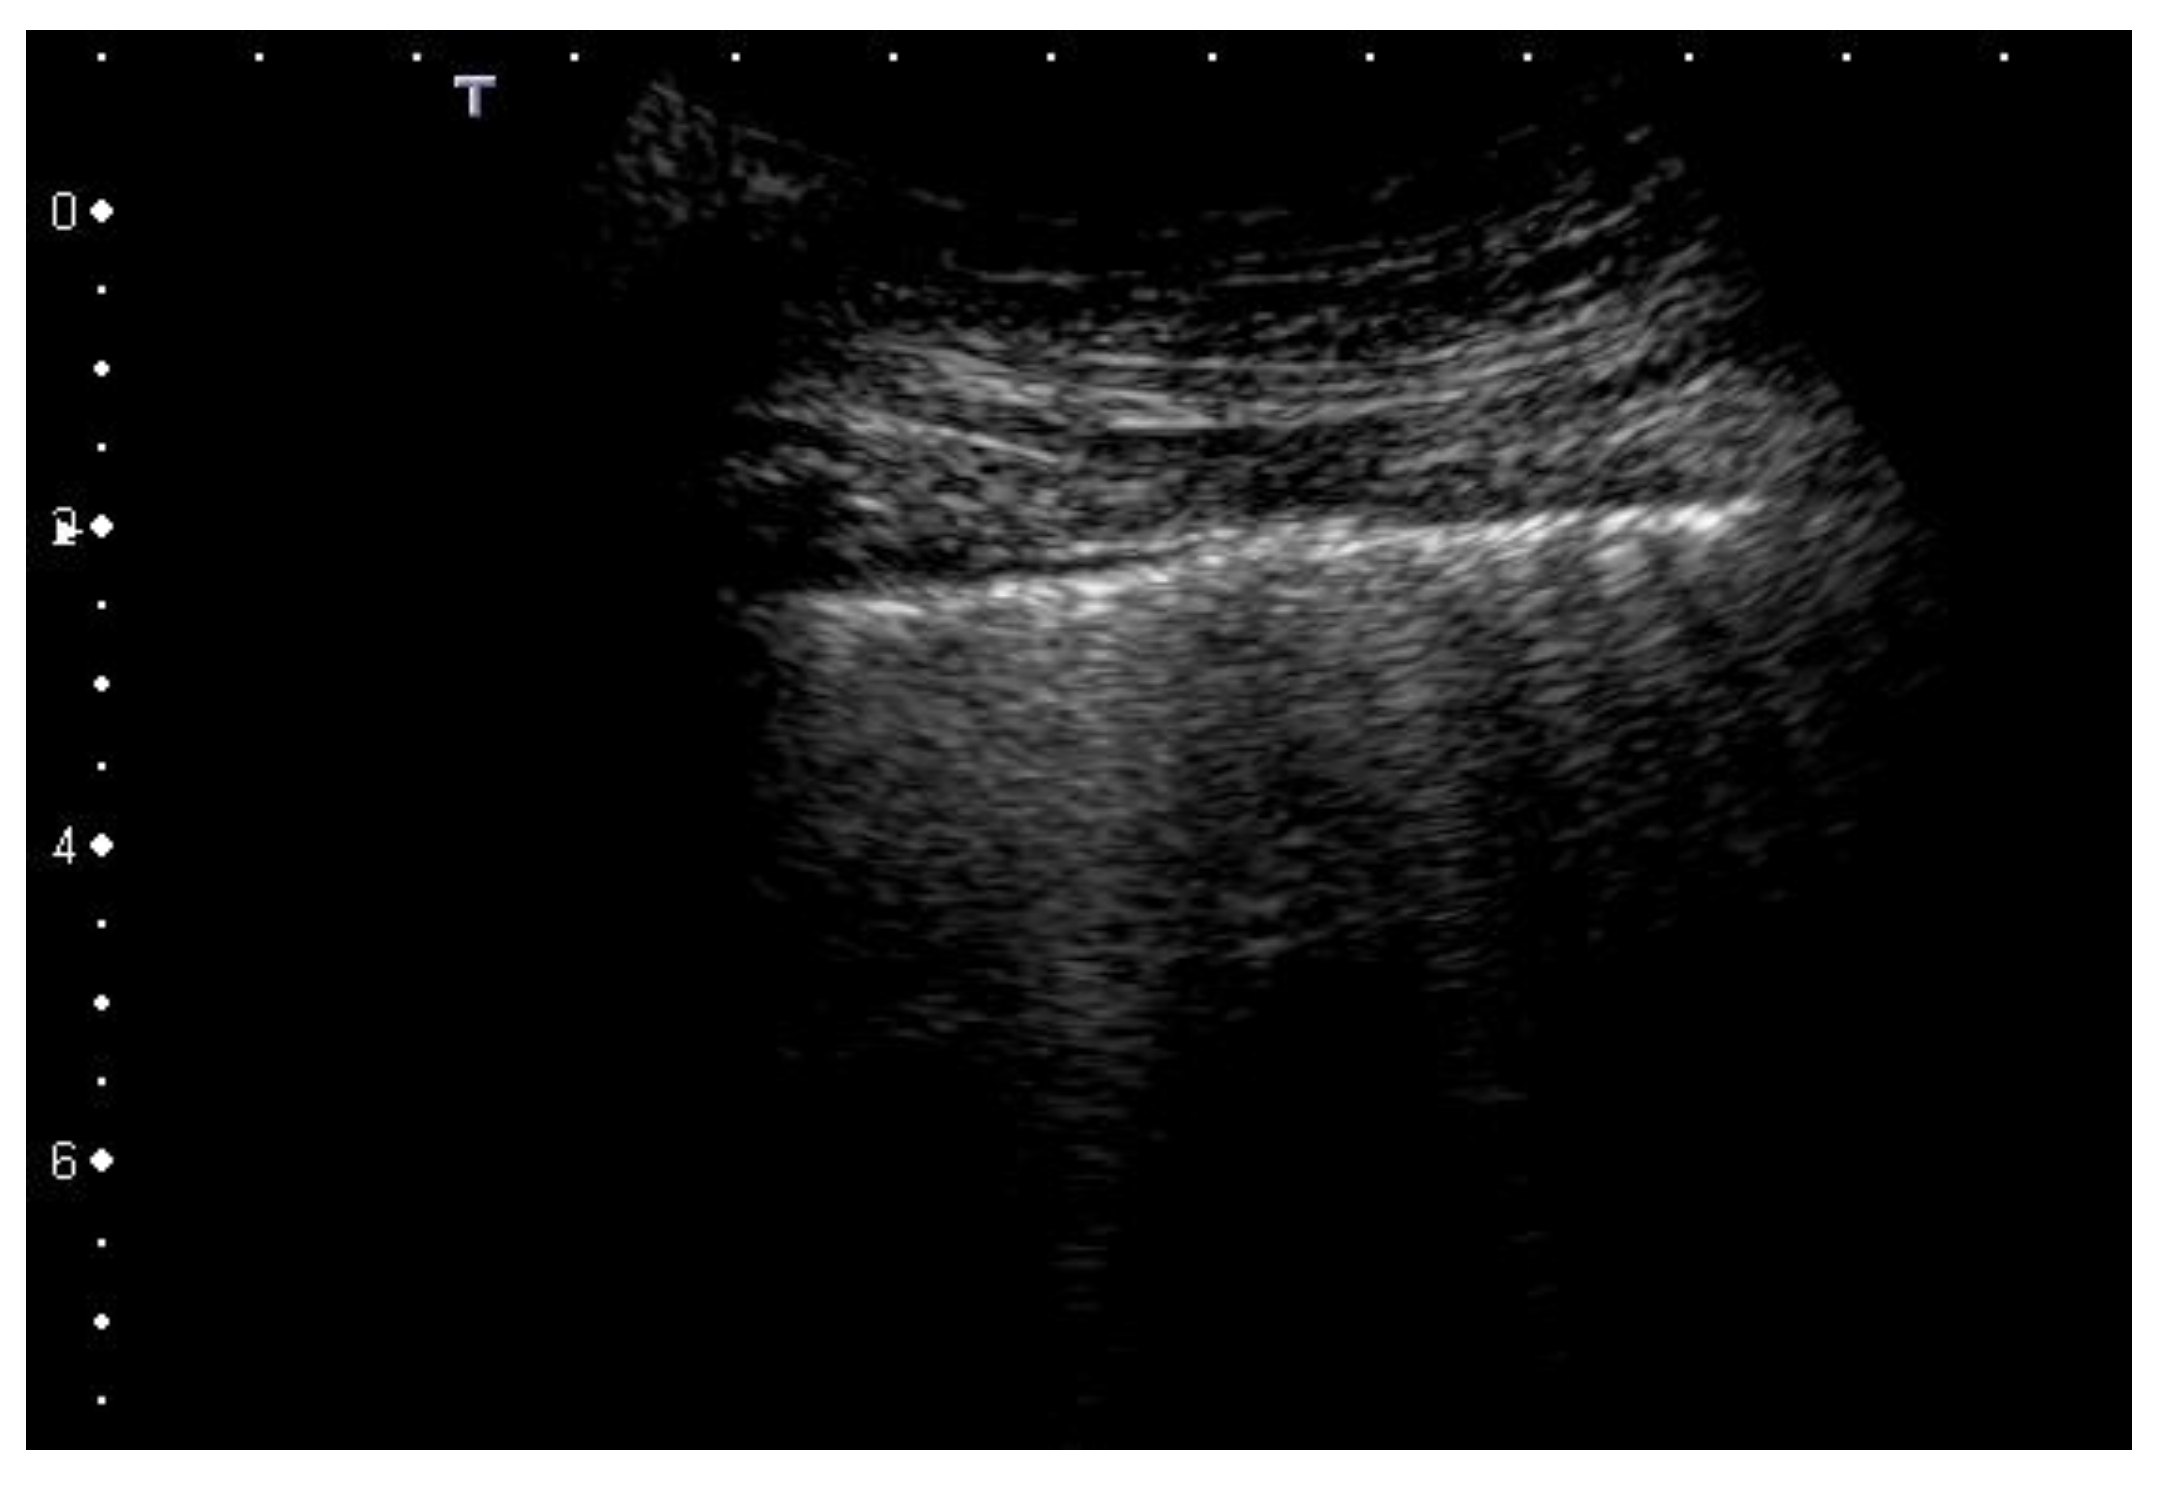

2.1. Characteristics of the Pleural Line

| 2 | Pleural line has relevant alterations. Progression of subversion of peripheral air space geometry causes a predominance of vertical artifacts. Small subpleural consolidations, related to deaeration, can be present. |

| 3 | Pleural line is irregular and cobbled. Subpleural lung is denser and more disordered. White lung with or without larger consolidations may be present. Small and large consolidations are subpleural regions minimally or completely deprived of air. |